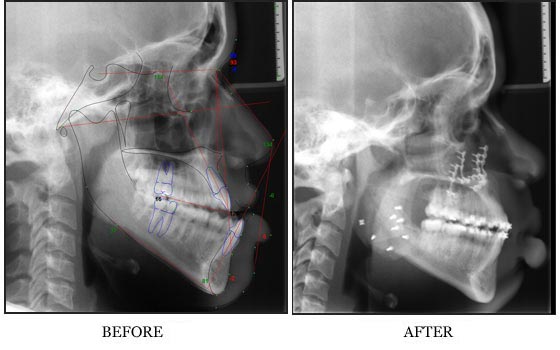

A maxillofacial surgeon and an orthodontist usually work as a team to evaluate and treat the problem in a comprehensive way. The main goals of orthognathic surgery are to achieve a correct bite and an aesthetic face. Nasal breathing problems may also be addressed at the time of surgery.

Sometimes, minor jaw problems can be managed by orthodontics on their own, but more complicated deformities can affect not only the appearance but the function of the jaw. These sorts of problems need a combined orthodontics and surgical approach. The chief object of orthognathic surgery here in San Francisco is to achieve the correct bite and restore the facial appearance.